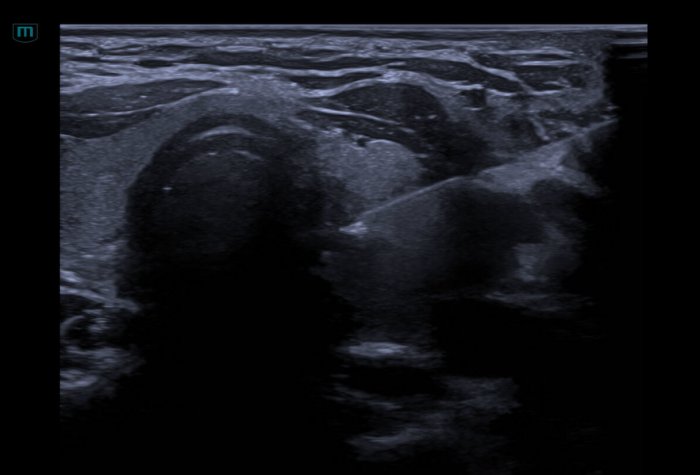

患者,女,30岁,在我院体检时发现甲状腺左叶多发结节,较大结节6×4×3㎜,纵横比>1,形态不规则,TR-RADS 4b。为进一步辨别结节的良恶性,拟行甲状腺细针穿刺,经综合评估,该患者适于FNA。

超声医学科主任殷志勇为患者进行超声引导下甲状腺结节细针穿刺活检术(FNA)。经超声引导,穿刺针精准进入病灶并取得了满意的标本。操作时间仅10分钟,整个术程顺利,患者无特殊不适。术后经病理科周新刚主任诊断,该例甲状腺结节的病理结果为可疑甲状腺乳头状癌(TBSRTC:V类)。